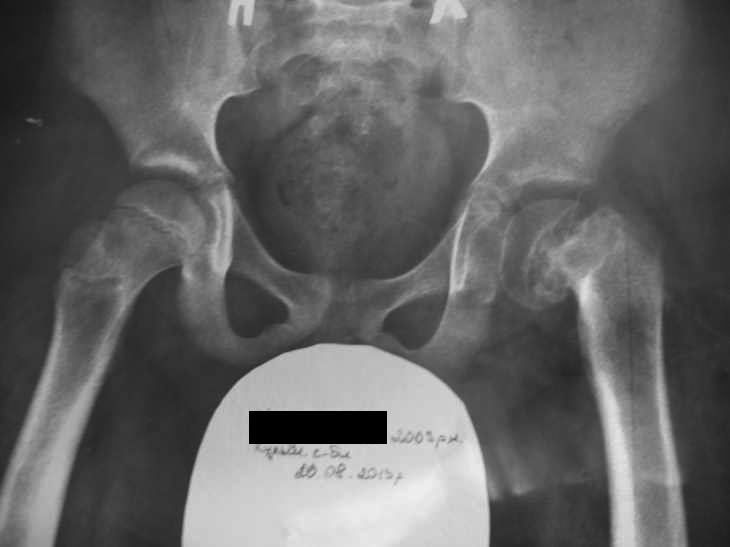

Здравствуйте,уважаемые коллеги.Обратился мальчик10-ти лет с болями в

левом коленном суставе.

Нами выставлен диагноз Юношеский Эпифизеолиз головки левой бедренной

кости. Передвигается самостоятельно без костылей.<>Из анамнеза болеет 6

месяцев . Амбулаторно лечили коленный сустав. Движения в тазобедренном

суставе ограничены, болезненны. Эпи- диафизарный угол слева 72 градуса

Подскажите, пожалуйста, тактику лечения.

Можно ли делать эпифизиодез и остеотомию бедренной кости одномоментно?